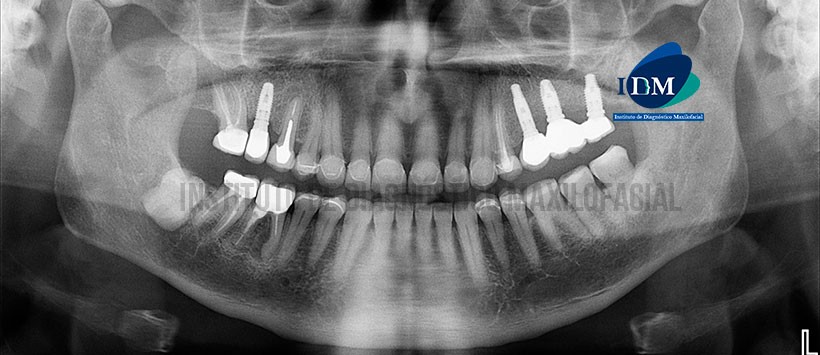

A la evaluación de la radiografía panorámica se evidencian múltiples implantes con prótesis sobre implantes, múltiples coronas protésicas, presencia de material de obturación de conducto en piezas 17 y 47, además de las piezas 15 y 46 material de obturación de conductos, espigos y corona protésica con proceso osteolítico en zona apical. Siendo lo mas resaltante la pieza 48, la cual esta retenida en posición mesioangulada con un aumento de la densidad radicular. (Figura 1)